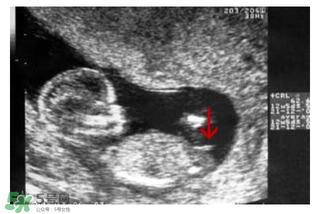

主要通过尾椎那里判断。 为了让大家更直观一些,我找两个比较明显的图,男左女右,大家看男孩儿的特征点与身体呈45度角,还多一些,而女孩儿的特征点几乎和躯体平行。图第一张男宝,第二张女宝

用线条表示一下就更直观了.当然,这也不是完全绝对的,如果你们发现自己的宝贝儿与心想的不一样,那这理论不一定对,不是绝对的.千万不要因为这个而影响自己孕期心情,宝宝健康是第一位的,我只是把自己所了解到的知识给大家普及一下。